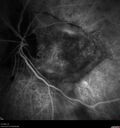

Most viewed - Optic nerve (disc) drusen and choroidal neovascular membrane 85 year old man - The left eye has had poor vision for 7-8 years. The right eye is OK. He was in for a checkup and his ophthalmologist noticed a problem and asked him to see retina doctor. Â

Medical Hx: Cancer.

Surgical Hx: Back Surgery. Gallbladder. Appendectomy. Colon Cancer.

Systemic Meds: Propafenone Hydrochloride, 225 mg oral tablet. Rosuvastatin. PAROXETINE HCL. GABAPENTIN. DONEPEZIL. Asp

VA OD: Dcc20/25-2 OS: DccCF 1ft

IOP: TP: OD:13 OS:12

Patient's right eye was treated with Avastin and was dry with one shot.